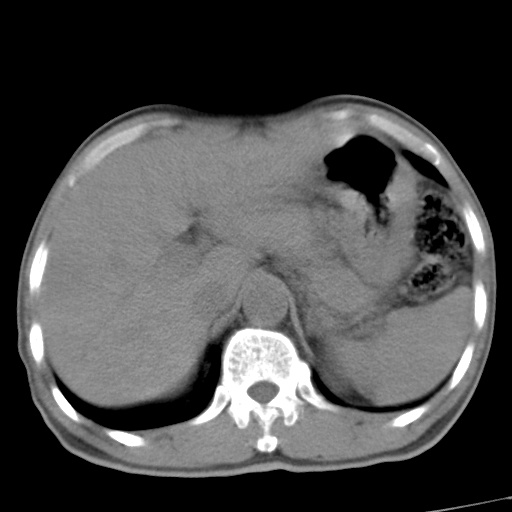

肝脏多发类圆形低密度影,考虑肝脏转移瘤,肝胃韧带一淋巴结肿大,原发?胃癌?

考虑胃癌肝脏转移可能性大。

考虑胃癌并肝脏及腹膜后淋巴结转移;不排除淋巴瘤。

肝内转移瘤,腹腔及腹膜后淋巴结转移。